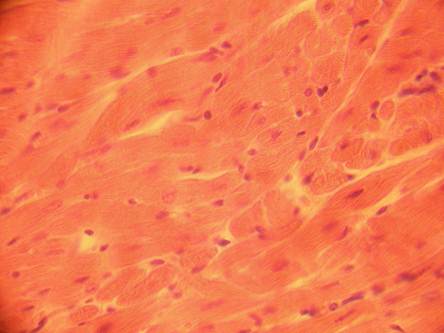

Фото 1.5.4. Стенка сердца. Миокард. Кардиомиоциты. Продольный срез Гем.-Эоз. Большое увеличение.(Ув.40х7)

| сократительный кардиомиоцит | |

| ядро сократительного кардиомиоцита | |